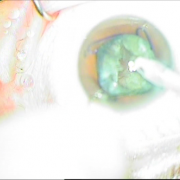

Μεταγχειριτική παρεκτόπιση ενδοφακού sun set syndrome

Μετεγχειριτική παρεκτόπιση ενδοφακού

Sun Set Syndrome

Συραφή του ίδιου φακού πίσω από την ίριδα

Συραφή του ίδιου φακού

πίσω από την ίριδα

Ευθυγραμμισμένος ενδοφακός